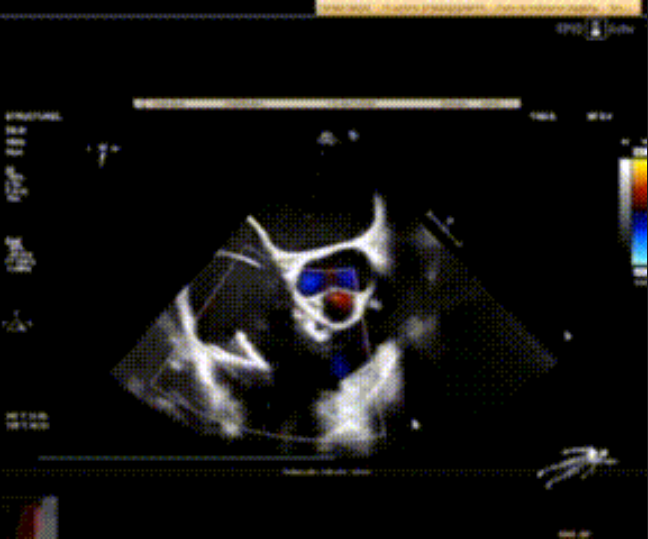

術(shù)前心臟超聲提示:極重度三尖瓣返流,右房容積明顯增大,三尖瓣瓣環(huán)顯著擴(kuò)張。

術(shù)后心臟超聲提示:LuX-Valve Plus植入后,三尖瓣瓣環(huán)處可見人工瓣膜回聲,未見返流,人工瓣膜穩(wěn)定,瓣葉開閉良好,連續(xù)多普勒估測(cè)三尖瓣平均跨瓣壓差僅為1mmHg。